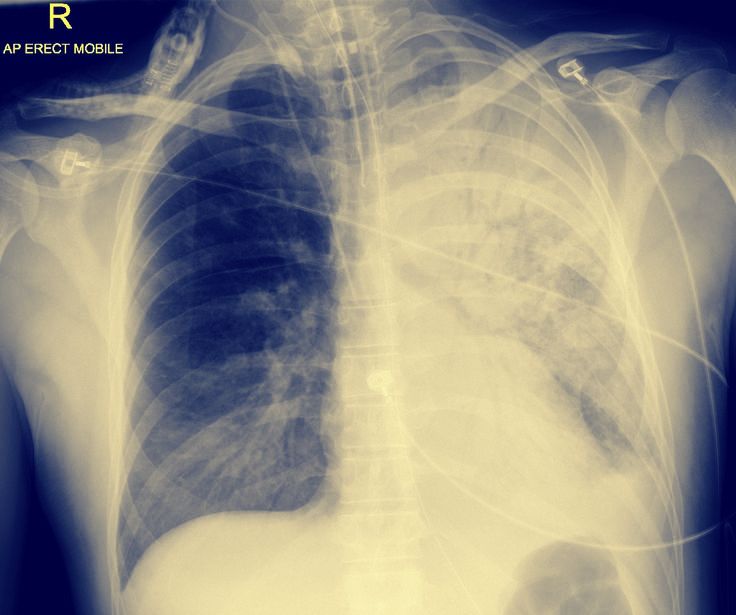

Lungröntgen och DT

• Fläckvisa förtätningar med groundglass-utseende.

• Oftast basalt och perifiert och i princip alltid bilateralt.

• Pleuravätska är ovanligt (<5%)